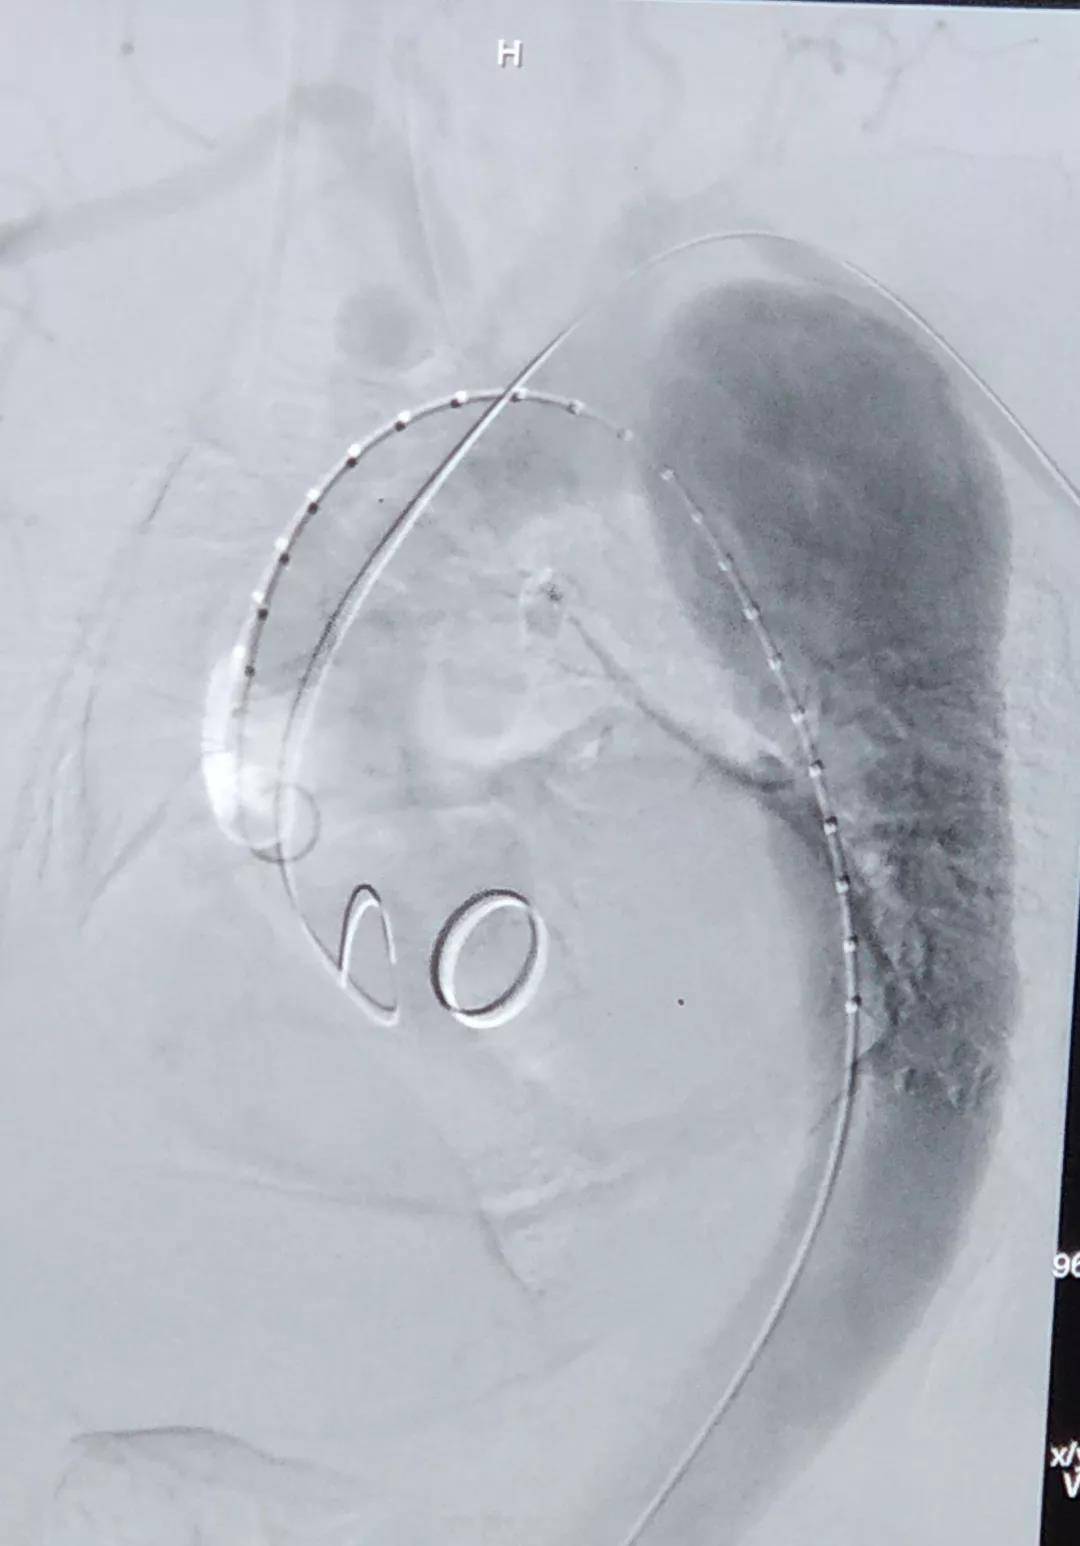

术中通过DSA造影显示:主动脉夹层破口位于左锁骨下动脉近端,真腔压闭。舒畅教授通过左锁骨下动脉预置Longuette™裙边支架,释放 Ankura™ Pro主动脉主体覆膜支架,封堵破口后通过裙边支架显影点准确定位,释放裙边支架,凭借着舒畅教授精湛的手术操作和器械的优异性能,手术过程非常顺利,胸主动脉支架释放良好,患者的主动脉夹层破口封闭良好,左锁骨下动脉释放的裙边支架血流通畅,没有内漏发生。由于患者远端真腔较小,为了保证远端的血流,植入了一个cuff支架,造影显示远端真腔打开良好。

(图:术前造影)

手术结束后的现场提问环节中,舒畅教授在回答关于术式选择的问题时讲到:由于患者破口很大,不适用于体外开窗的方式;且患者左锁骨下动脉相对比较扭曲,与主动脉弓有成角,采用原位开窗的方式比较困难,因此选择了平行支架(即烟囱)的方式进行处理。此病例选择的彩神在线网信彩票-彩神通免费版下载-彩神8争霸vlll-彩神购彩购彩大厅-彩神软件陆立根免费版-彩神ll争霸3-彩神ll彩神8-彩神ll争霸彩票-拼搏在线彩神网网页版Longuette™裙边支架,其独特的外柔内刚的设计,可巧妙的解决烟囱技术中的内漏问题。同时,舒畅教授还提到,Longuette™裙边支架共有4个显影点,DSA下显影良好,可确保术中精准定位。同时,Longuette™支架的内层结构相对裙边适度加长,适宜的长度可在防止大支架将分支支架遮蔽的同时保证分支支架不遮挡左颈总动脉。彩神在线网信彩票-彩神通免费版下载-彩神8争霸vlll-彩神购彩购彩大厅-彩神软件陆立根免费版-彩神ll争霸3-彩神ll彩神8-彩神ll争霸彩票-拼搏在线彩神网网页版新型主动脉支架系统在防堵、防漏、防疲劳方面都进行了周全的考虑,是主动脉疾病的腔内治疗在主动脉弓部方向上的创造性突破。